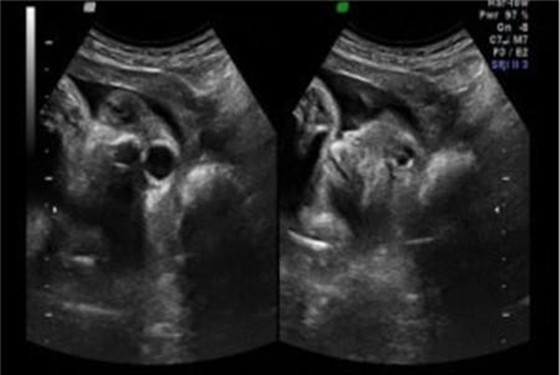

从以上怀孕五个月的胎儿彩超图可以看出,小宝宝的五官(分得出眉毛和眼睑的界线)和四肢(宝宝的手指和脚趾都已经长出了指甲)已经差不多发育成熟了,而且身体的各个器官(味觉,触觉,听觉,嗅觉)功能也在逐渐完善中,胎儿的性器官(生殖器)已经发育得非常明显了,此时通过B超检查完全能分辨出男孩女孩了。